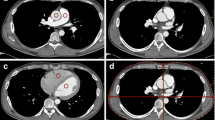

By calculating the tube-current-time settings equal to the patients weight in kilograms multiplied by four in milliampere seconds (group A2), an optimised dose distribution was achieved while retaining a nearly unimpaired diagnostic image quality. The average image quality according to the consensus assessment was 1.5±0.5 for group A1, 1.6±0.5 for group A2 and 1.7±0.7 for group B. No examination in any of the subgroups was rated as poor (score of 4) or non-diagnostic (score of 5) (Figs. 1, 2).

MPR of a male patient (76 kg, 1.69 m; group B). Tube current-time settings: 300 mAseff 120 kV. The left anterior descending coronary artery (LAD) is clearly depicted and unrestrictedly evaluable. After dose reduction, even small diagonal branches of the LAD are still uncompromised accessible (arrows)